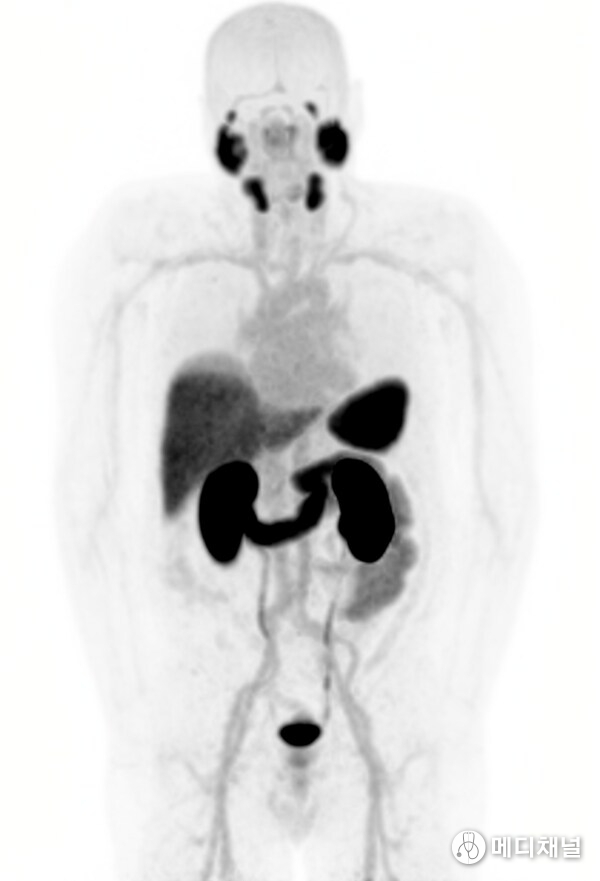

Trial participant with no detectable disease after 3 cycles of 67Cu-SAR-bisPSMA

One of the participants in the Cohort Expansion was a 64-year-old man with bone metastases and baseline PSA of 5.4 ng/mL prior to entering the SECuRE study. Following his first cycle of 67Cu-SAR-bisPSMA, this participant showed a dramatic 95.2% reduction in PSA. He went on to receive 2 more cycles of 67Cu-SAR-bisPSMA and achieved undetectable PSA levels. In a follow-up bone scan and CT no metastatic disease was observed. This participant only exhibited mild (Grade 1) related AEs, most of which were gastrointestinal events, with no haematological or renal AEs observed. The participant reported having excellent quality of life following the treatment.

"All of the participants with evaluable data treated in the Phase II to date have shown declines in PSA, with the majority showing PSA decreases of more than 50% and mostly having only mild or moderate AEs. Most of these patients have been treated with more than 5 systemic treatment regiments and had bone metastasis prior to entering the SECuRE study. Although the number of participants with evaluable data to date is small, it is incredible to see yet another extraordinary case where a patient who had bone metastasis prior to entering the study achieved undetectable PSA following 67Cu-SAR-bisPSMA treatment, with no disease observed by anatomical and molecular imaging at the last assessments. This participant only experienced mild, transient AEs, most being gastrointestinal, and has reported having excellent quality of life following the treatment.